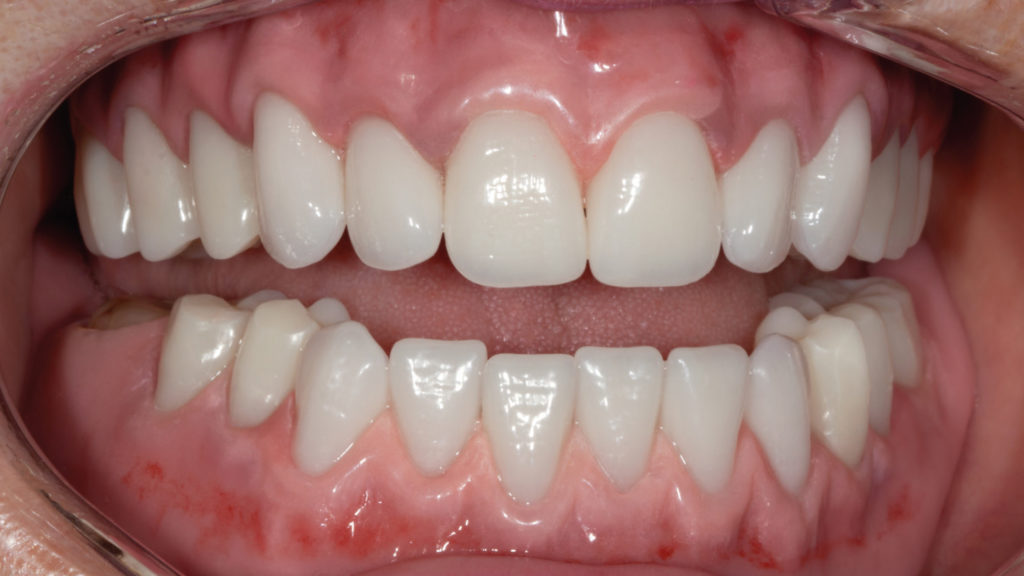

Ausarbeiten und Einprobe

Da der Verlauf der Gingivagirlande nicht durch einen stufenförmigen Übergang zwischen Zahn und Zahnhals festgelegt ist, sondern natürlich verläuft, konnte die mukogingivale Architektur patientengerecht modelliert werden (Abb. 8). Auch die Alveolarfortsätze, Gaumenfalten und Gaumennaht sowie die Papilla incisiva wurden in Wachs umgesetzt, um bei der klinischen Einprobe die finalen Prothesen so gut wie möglich zu simulieren (Abb. 9 und 10). Nach sorgfältiger Prüfung wurden die Seitenzähne mehr nach distal positioniert, um ein individuelleres und deutlich natürlicheres Erscheinungsbild zu erzielen. Der einzelne Zahn 46 wurde zirkulär von der Basis eingefasst, um der oberen Aufstellung mehr okklusale Stabilität zu geben und die Verschiebung des Zahnes nach distal zu kompensieren. Die Patientin kam phonetisch und funktionell gut zurecht und zeigte sich von der natürlichen Wirkung der Konfektionszähne begeistert (Abb. 11). Durch seinen dreidimensionalen anatomischen Aufbau in multiplen Schichten und den harmonischen Farbverlauf vom Hals bis zur Schneide wirkte die Frontzahngarnitur Vitapan Excell sehr lebendig. Seine naturgetreue Morphologie und nuancenreiche Oberflächentextur sorgten schon bei der Einprobe für ein brillantes Farb- und Lichtspiel im Patientenmund. Die markante Schneidecharakteristik mit weißlichem Inzisalsaum und integrierter Mamelonstruktur führte zu einer organischen Farbwirkung, die ausgewogene Transluzenz gleichzeitig zu einer naturgetreuen Lichtdynamik.

Der Fall zeigt, dass mit den richtigen Konfektionszähnen nach dem ästhetischen Regelwerk und Freude an der zahntechnischen Kunstfertigkeit totalprothetische Rehabilitationen entstehen können, die den Vergleich mit aufwendigen keramischen Ganzkieferversorgungen nicht scheuen müssen (Abb. 15). Die Patientin war von dem hochästhetischen Ergebnis und dem stabilen Sitz ihrer neuen Prothesen begeistert und zeigte unmittelbar nach der Eingliederung ein neues Selbstbewusstsein. Die Konfektionszähne zeigten ein lebendiges Lichtspiel und gaben der Patienten ihr altersgerechtes Aussehen zurück (Abb. 16 bis 18).